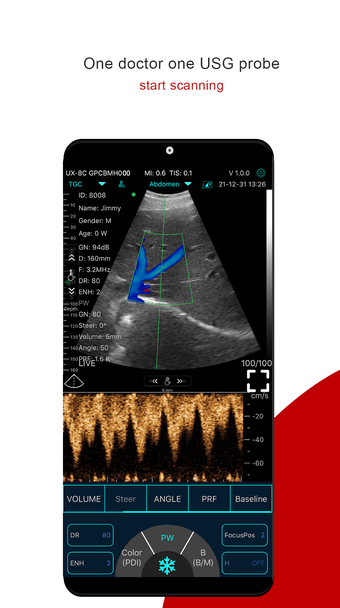

Мой USG — это первое соединение между зондом и интеллектуальному терминальному устройству необходимо ввести пароль Wi-Fi.